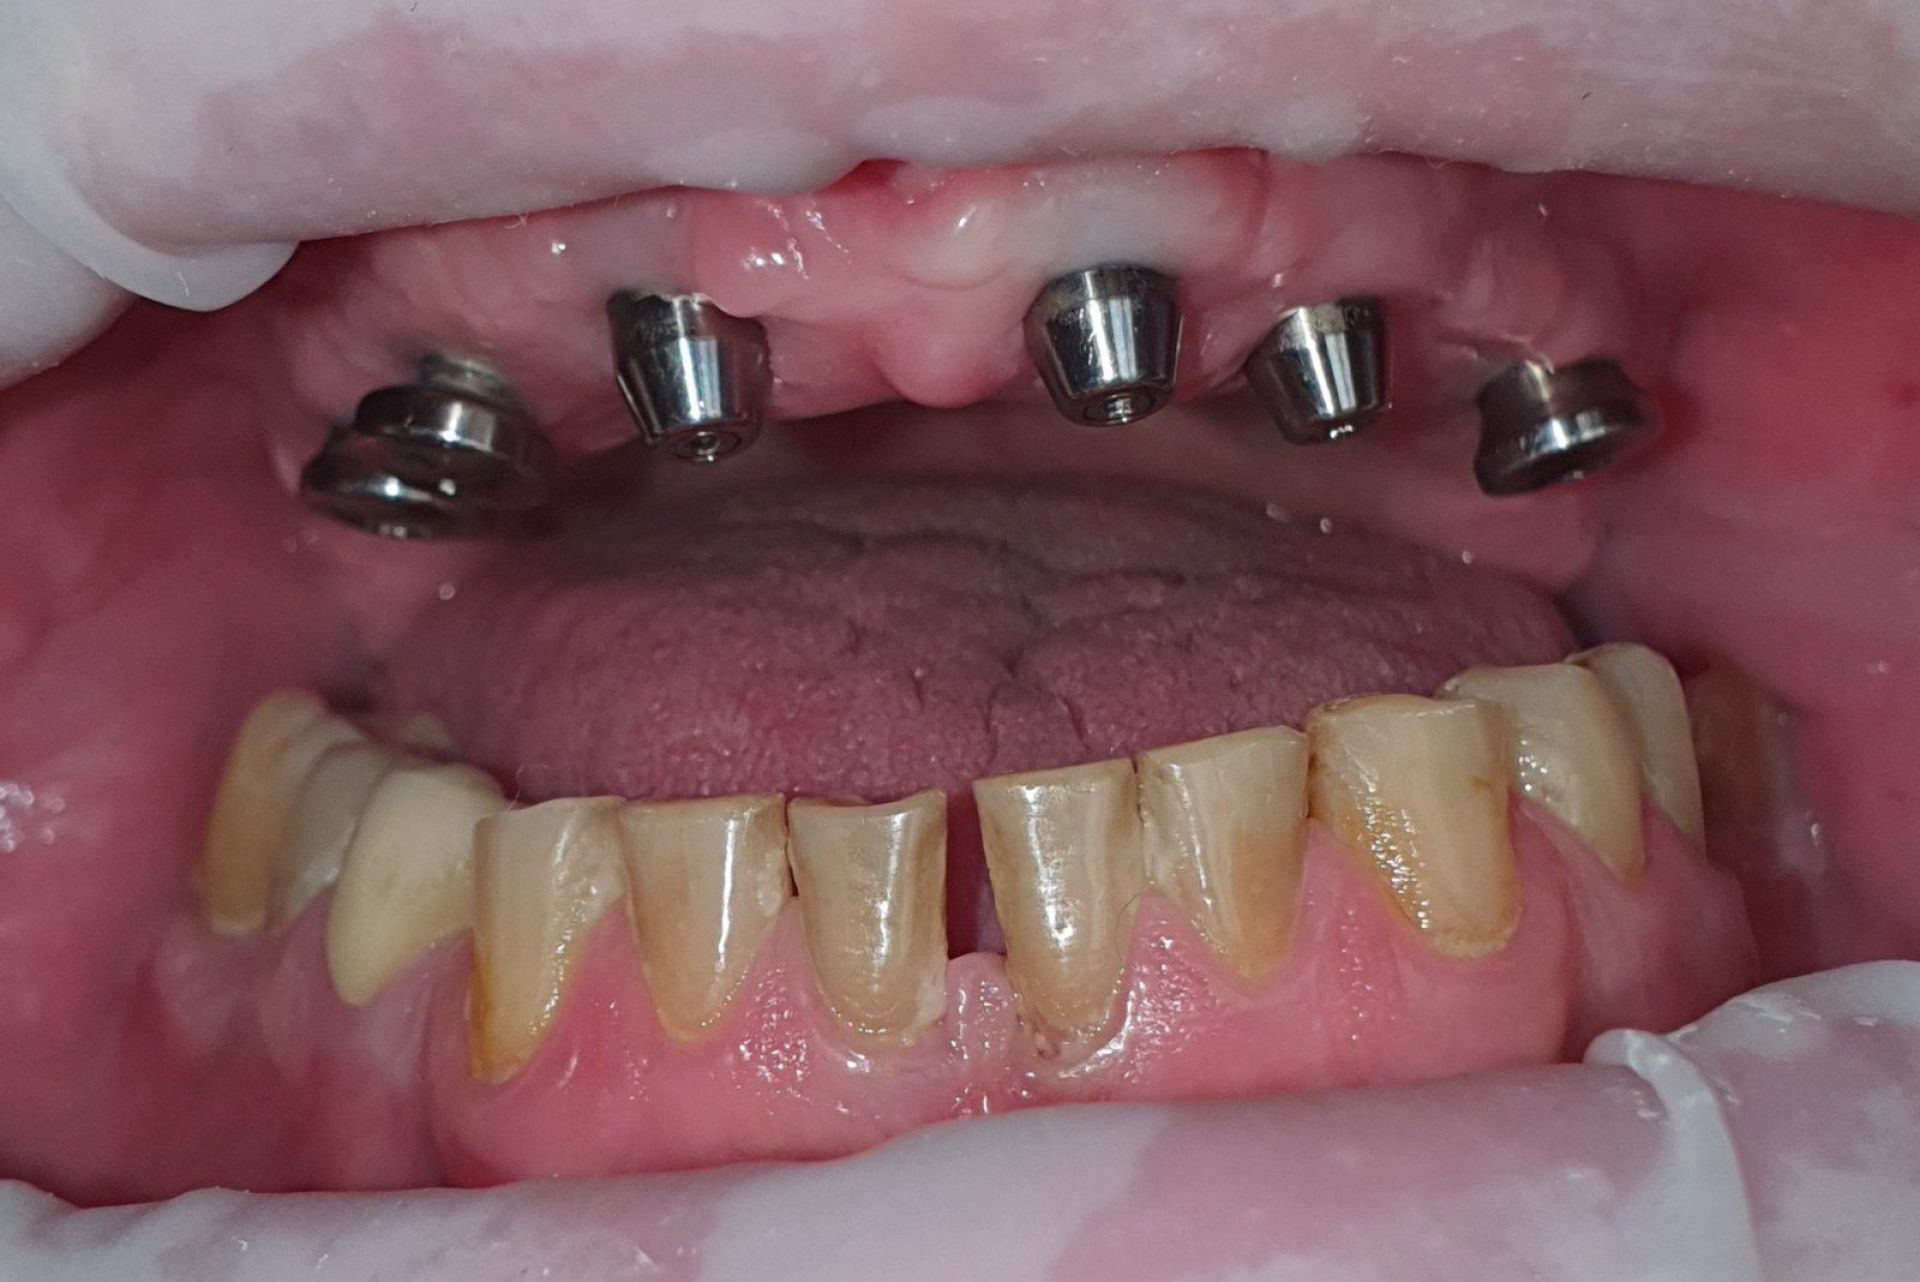

Імплант – це штучний корінь зуба, який виготовляється з титану. Він хірургічно вставляється в щелепну кістку, на ньому фіксується коронка, міст або протез. Імпланти відновлюють не лише естетику посмішки, але й функціональність зубів, даруючи Вам комфорт та впевненість.

Як відбувається сам процес імплантації в AsProDent:

- в місце відсутнього кореня вживлюється титановий імплант

- після приживлення імпланту, а це від 2-х до 6-ти місяців встановлюється формувач ясен

- пізніше встановлюється абатмент та тимчасова коронка

- завершальним етапом буде встановлення постійної коронки

Техніка одномоментної імплантації: сучасна методика, під час якої встановлення імпланту проходить одразу після видалення зуба. Фактично, дві складні процедури (видалення зуба і встановлення імпланту) виконується за один візит, Але у випадках, коли пацієнт потребує відновлення давно втрачених зубів, лікар розглядатиме інші техніки.